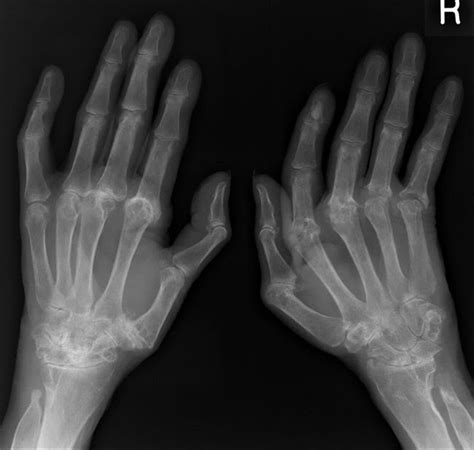

In some cases, a sagittal band rupture can occur due to degenerative changes in the tendons and ligaments, which may be more common in older individuals or those with pre-existing conditions like rheumatoid arthritis.